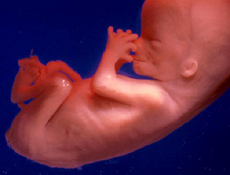

- Fóstrið mælist nú 11,5-13 sm og vegur tæplega 100 gr.

- Neglur eru komnar á fingur.

- Mögulega geta fjölbyrjur þ.e. konur sem hafa gengið með börn áður fundið hreyfingar fóstursins. Í byrjun líkist þetta fiðrildaflögri eða meltingarskruðningum og konan er ekki viss hvort þetta séu hreyfingar eða ekki Einn góðan veðurdag fer það þó ekki á milli mála, þetta eru hreyfingar.

- Magn legvatns er um 180 ml.